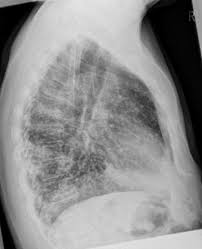

Granulomas are often found incidentally on an X-ray or other imaging test done for a different reason. Calcified granulomatous disease does not appear to aggregate in families. Calcification of the granuloma causes the.

Because it usually takes some time for calcium to be deposited in a granuloma it is generally assumed that a calcified granuloma is an old granuloma or an old area of inflammation. Calcified granulomas can also form from fungal infections such as histoplasmosis or aspergillosis. Determinants influencing patterns of granulomatous disease include occupation age and geographic location.

A calcified granuloma is a mass within a particular organ typically the lungs that has calcified. Granulomas frequently occur in the lungs but can occur in other parts of the body and head as well.